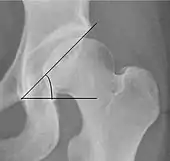

| Tönnis angle | ![]() |

Slope of the sourcil (the sclerotic weight-bearing portion of the acetabulum) | 0 to 10°

|